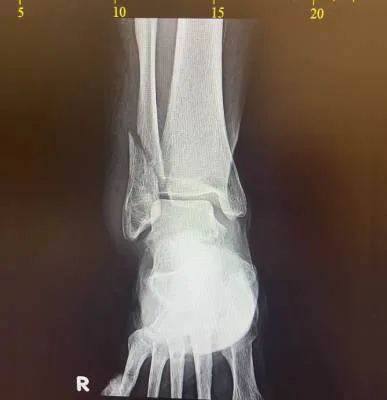

Dr. Haytham Elkhatib is a distinguished orthopaedic surgeon specializing in comprehensive musculoskeletal care. With expertise in trauma, fracture treatment, and advanced interventional joint injections, he offers innovative solutions for various conditions.

I had surgery with Dr. Haytham, and I’m very happy with the results. He previously operated on my leg after a fracture, and that surgery was very successful. Recently, I had another surgery on my knee, which was done in the simplest and most professional way. After the operation, I was able to return to my normal life — I can play football and be active again after a long time of not being able to. Dr. Haytham and his team took great care of me throughout the process, and I truly thank him for his excellent work and dedication